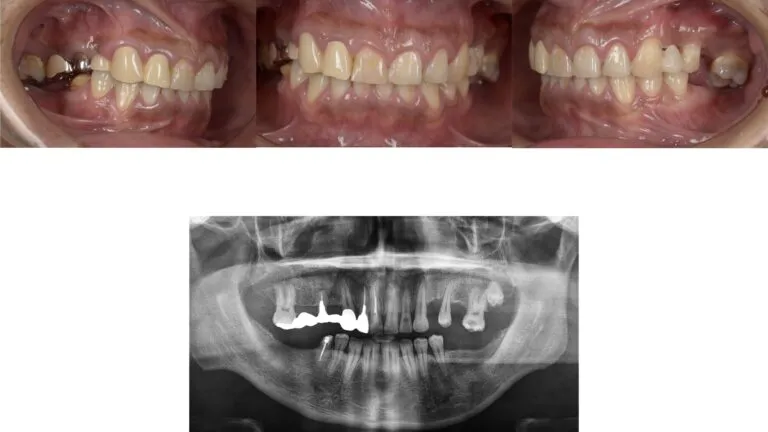

症例2

- 主訴

- 歯が取れた。全体的な治療を希望

- 治療内容

- インプラント治療、下顎前歯の部分矯正、セラミックによる補綴治療

- 治療費

- 400万

- 治療期間

- 1年6ヶ月

- 通院回数

- 60回

- 想定されたリスク

- 歯根破切や補綴装置の脱離

- コメント

- これまで局所的な治療の繰り返しを受けてきていた為、噛み合わせなども考慮して全顎的に整えることができた

before

after